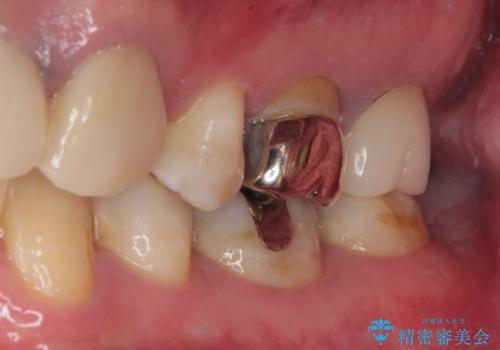

拡大鏡視野下で、保険のプラスチック、虫歯の除去を行い、セラミックインレーに適した形に整えました。

歯と歯茎の間に圧排糸と言われる糸を入れてシリコーン印象材にて精密な型どりをしました。

セラミックインレーの装着時には、唾液の侵入を防ぐために、ラバーダム防湿を行いました。